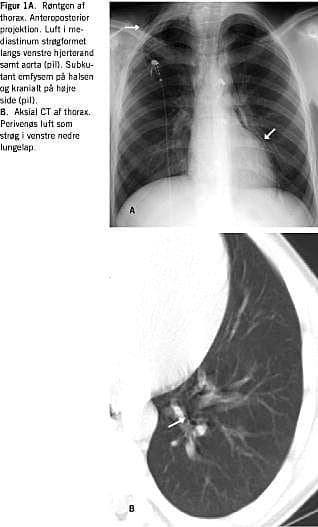

Røntgen af thorax i anterior-posterior-projektion (Figur 1A ) viste luft i mediastinum som vertikale strøg specielt langs venstre hjerterand og aortabuen. På halsen og kranialt på højre side sås subkutant emfysem. Røntgen viste ikke lungeinfiltrater eller tegn på pneumothorax.

Ved en CT af thorax (Figur 1B) sås der luft perivenøst i nedre venstre lungelap. En rumperet perifer bronkie eller alveole kunne således være årsag.

Summary Spontaneous pneumomediastinum: a rare cause of chest pain Ugeskr Læger 2004;166:4168-4169 Spontaneous pneumomediastinum is a rare condition caused by a bronchial or alveolar rupture. We present the X-ray and CT findings in a patient in whom the condition occurred after playing soccer. The CT scan demonstrates the position of the alveolar rupture and the passage of air along the veins to the pericardium and mediastinum.